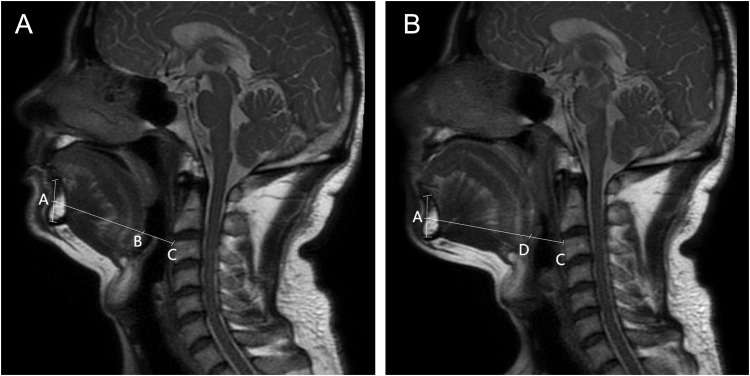

Patients and methods: Patients with OSAHS diagnosed by polysomnography (PSG) from February 2025 to March 2025 were included in this study, and UADMR was performed to detect the obstructive levels (palatopharyngeal level, root of tongue level, and epiglottic level) and assess the degree of obstruction at the root of the tongue and epiglottic levels. Subgroup analyses were performed according to different obstructive characteristics and the results of UADMR were assessed for correlation analysis with the results of PSG or manual titration of positive airway pressure. This study used Müller maneuver to simulate the airway collapse during sleep.

Results: A total of 34 OSAHS patients were included in this study. It was observed that the hypopnea index, apnea hypopnea index, and tongue axial change ratio were significantly higher in OSAHS patients with multiple layers of airway obstruction than in those with palatopharyngeal obstruction only. The anteroposterior diameter change ratio at the level of the root of the tongue and the area change ratio at the level of the epiglottis in patients with OSAHS were positively correlated with the results of the PSG, and the tongue axial change ratio was positively associated with the results of the manual titration of positive airway pressure.